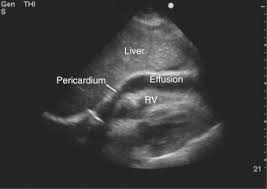

An Ultrasound Pericardial Effusion is a scan of the heart to identify the fluid accumulation in the pericardial surrounding the heart, and in the pericardial cavity, which can disturb the heart function. It can be caused by infections like viral bacteria, lupus, arthritis, malignancies etc.

Pericardial Effusion can have symptoms like chest pain, breathing problems, feeling of hardness in the chest. The scan of ultrasound of pericardial effusion detects the problem and diagnoses it and also visualises the fluid level in the heart, size of the heart, and functioning of the heart.